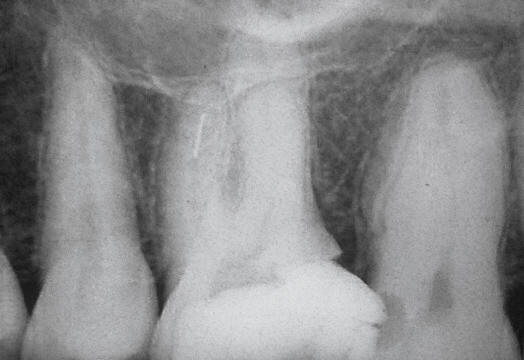

Fractura de lima en tercio apical

En el tercio coronal las posibilidades de remoción son optimas. Si el instrumento se fractura en el tercio medio y apical las posibilidades de remoción son muy bajas, por esto debe tener en cuenta ¿En que etapa de la instrumentación se ha fracturado un instrumento?